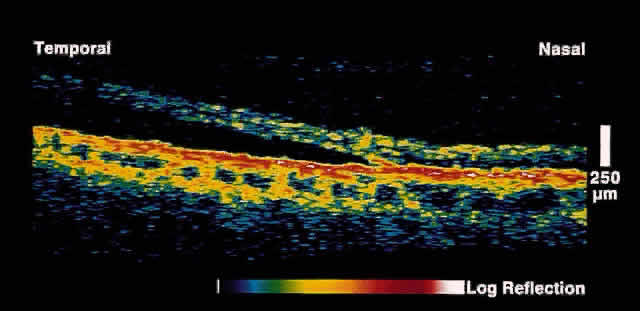

Retinal Detachment and Retinoschisis

Full-thickness retinal detachment can usually be distinguished from degenerative retinoschisis on the basis of clinical features alone. However, in some cases this is difficult; various ancillary tests such as laser photocoagulation, visual field evaluation, and B-scan ultrasonography can be helpful but are not always definitive. OCT is an objective and reliable method to distinguish the two entities.17 In retinoschisis, OCT images show splitting of the neurosensory retina consistent with the known histopathology of a separation at the outer plexiform layer (Fig. 14). Retinal detachment presents as a separation of full-thickness neural retina from the underlying RPE band (Fig. 15). Although lesions anterior to the equator cannot be imaged by OCT, most lesions that are posterior to the equator, or that have a component posterior to the equator, can be effectively imaged.

Fig. 14. OCT image through peripheral retinal elevation suspected to be retinoschisis versus retinal detachment. This image shows a splitting of the neurosensory retina consistent with retinoschisis.

Fig. 15. OCT image through peripheral retinal elevation suspected to be retinoschisis versus retinal detachment. This image shows a full-thickness detachment of the neurosensory retina consistent with a retinal detachment. In contrast to retinoschisis, splitting of the neurosensory retina is not present.